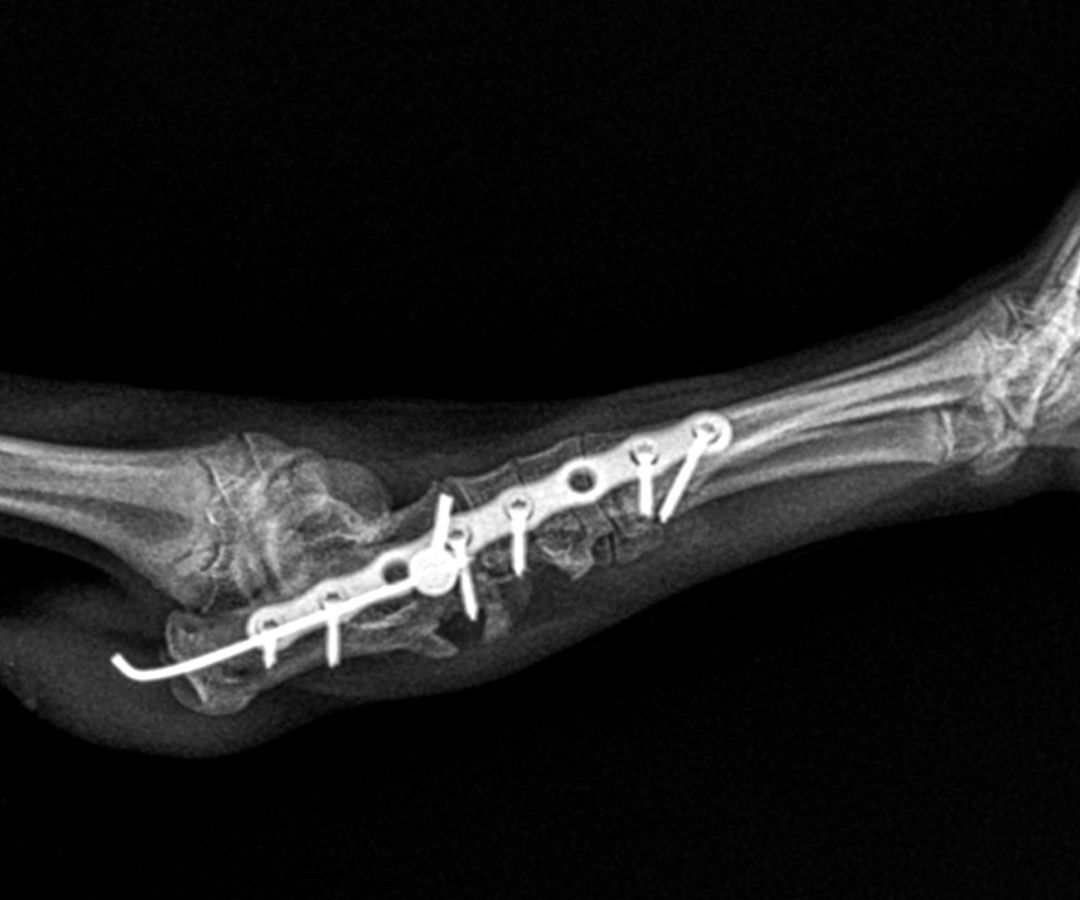

The first priority was bringing the broken heel bone back into alignment. A fine pin (1.1 mm intramedullary pin) was passed retrogradely through the calcaneal fragments, essentially acting as an internal scaffolding rod, holding the pieces together while the more complex reconstruction took place around them.

With the heel bone provisionally stable, the team turned their attention to Ralphie’s dislocated joints. Because several of the small tarsal joints had been thrown completely out of position, they needed to be temporarily bridged and held still to allow the disrupted ligaments time to heal. A slim, precision locking plate (a 1.5 mm 8-hole RL Leilox plate) was secured along the outer side of the ankle region. This specialised implant bridged across the small bones of the hock joint, running from the metatarsal (foot) bones, through the central tarsal and fourth tarsal bones in the ankle, and anchoring into the calcaneus (heel bone). This provided stability across the affected area.

Locking screws anchored at multiple points meant that the load was distributed across the repair rather than concentrating stress at any single fixation point, which is particularly important in a puppy's developing bone. An additional cortical screw fitted with a small washer was inserted through the lower fragment of the calcaneus (heel bone) and into the talus (the bone sitting directly above the heel) to further strengthen and stabilise the overall repair.

Post-operative X-rays confirmed that the fractured bones had been successfully realigned and that all implants were correctly positioned.